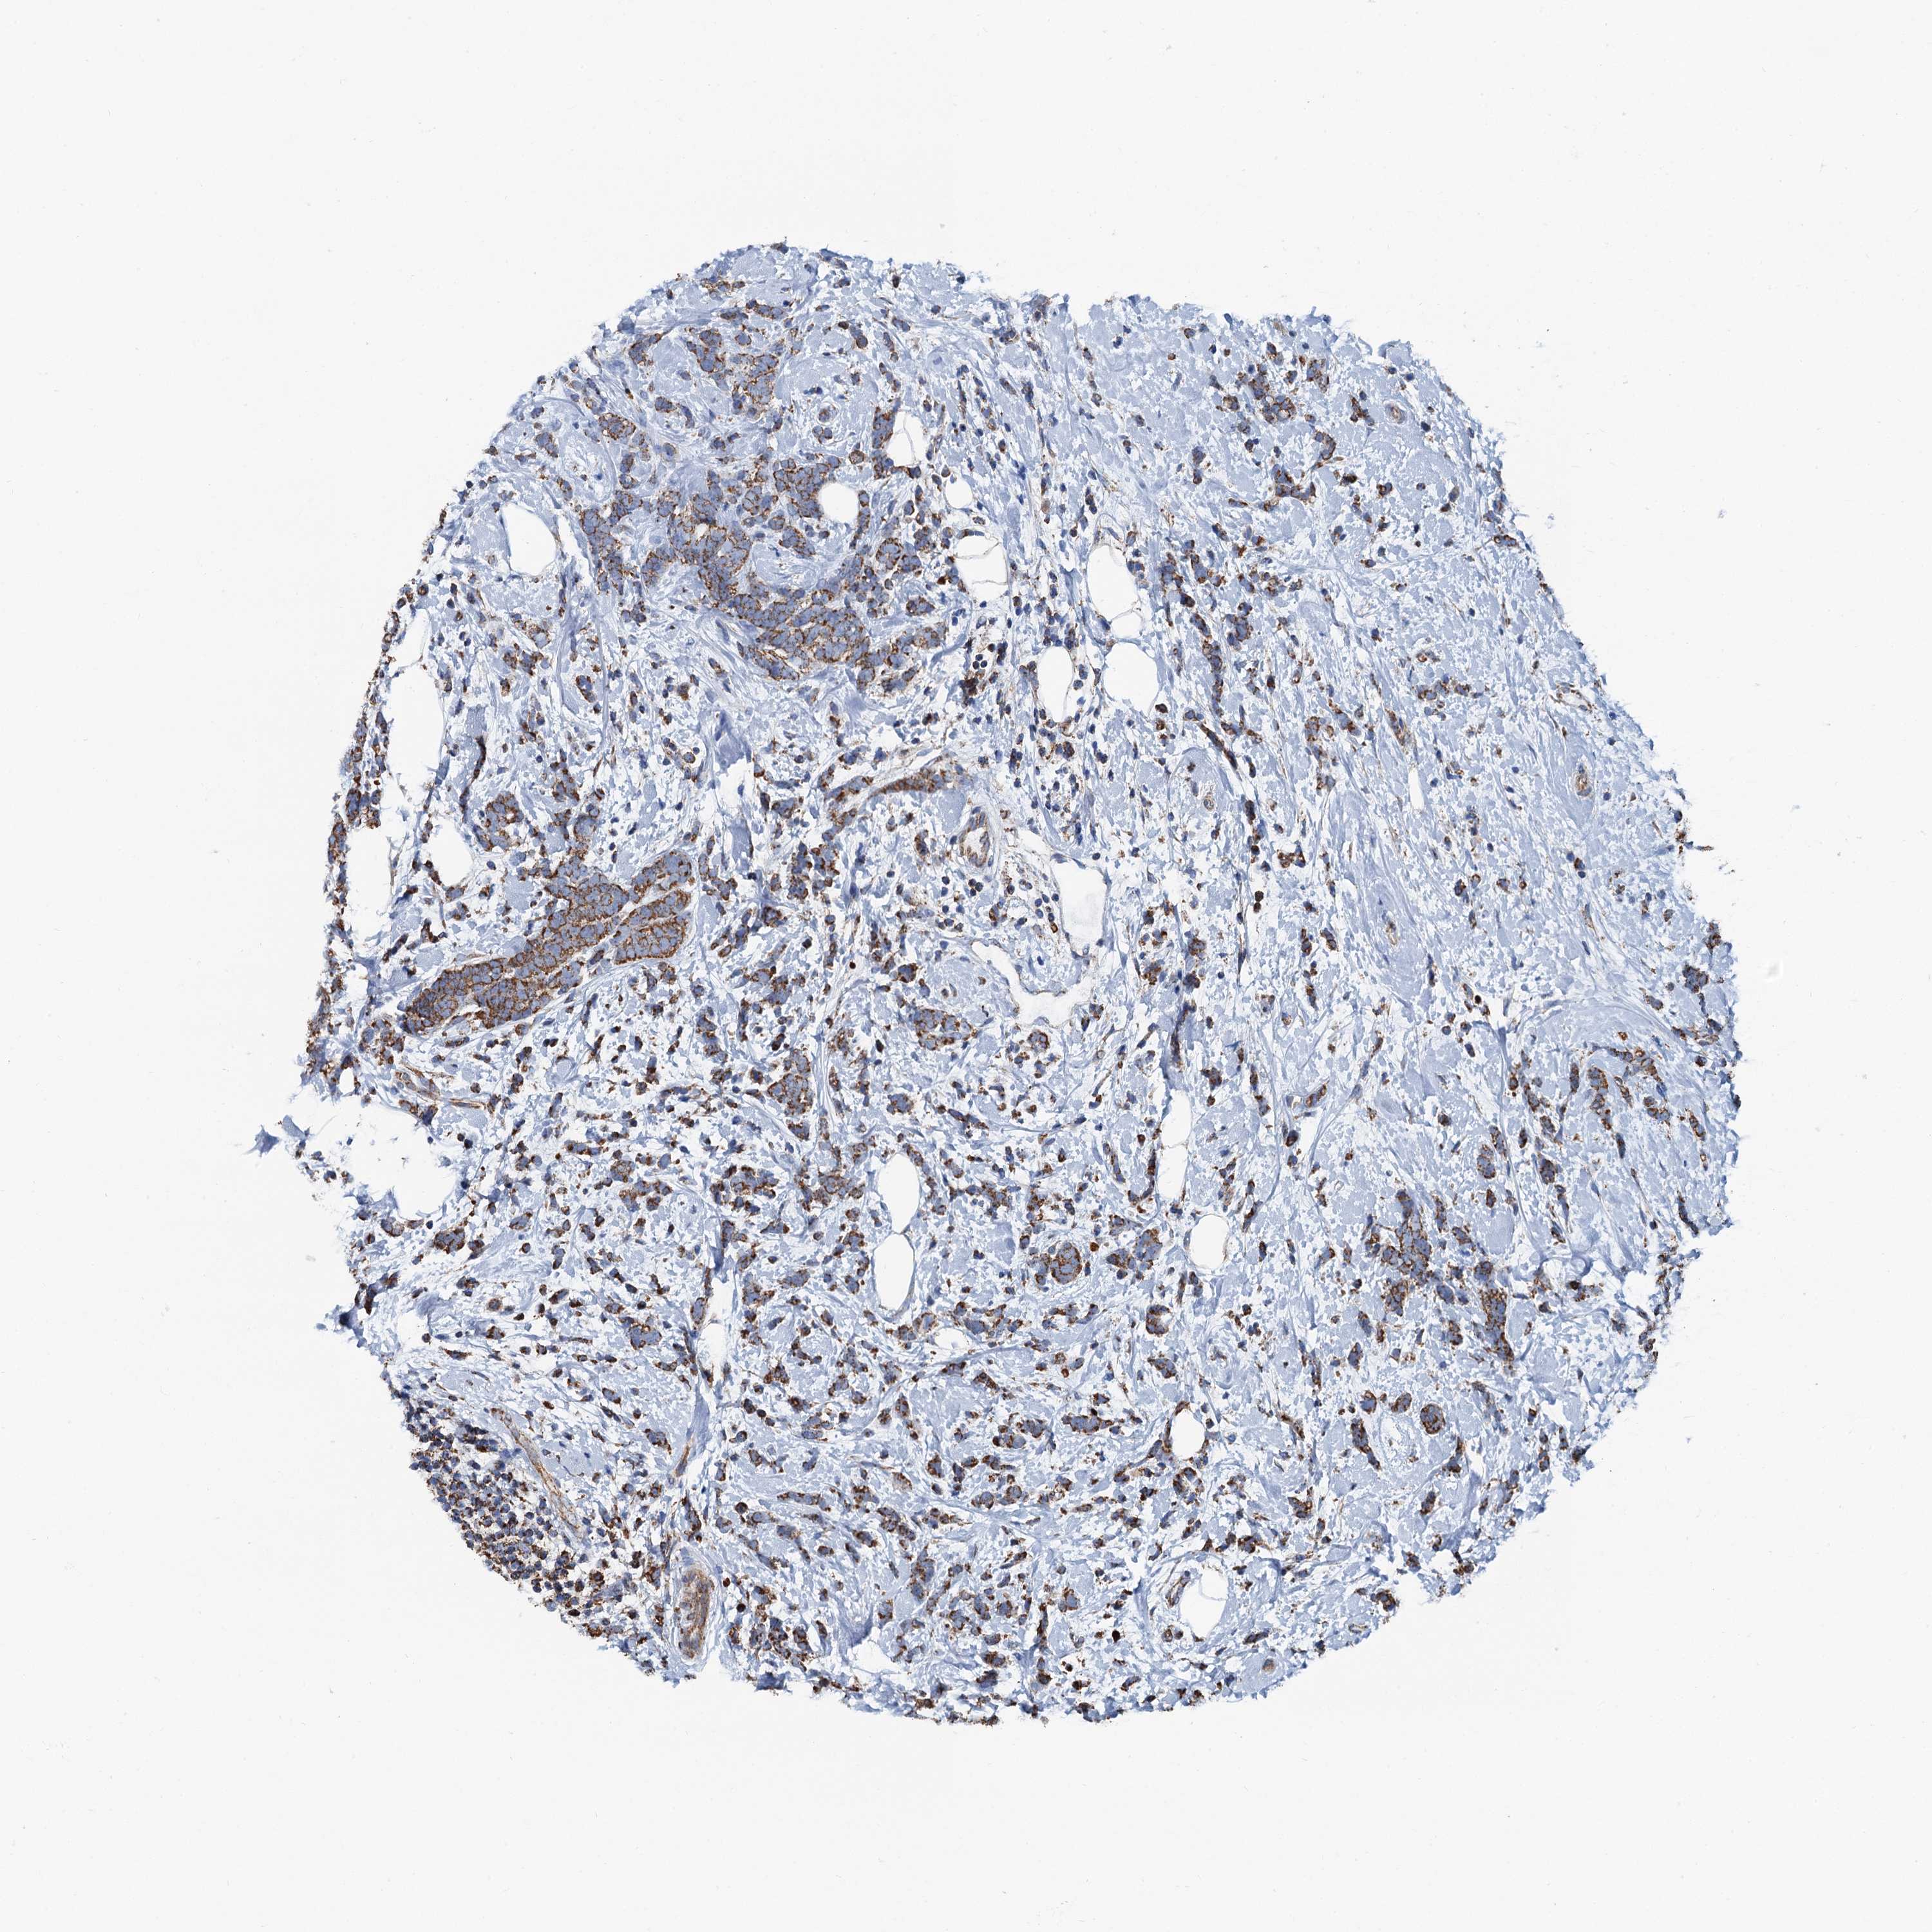

CANCER BREAST CANCER Show tissue menu

BRCA TCGA BRCA VALIDATION PROTEIN EXPRESSION